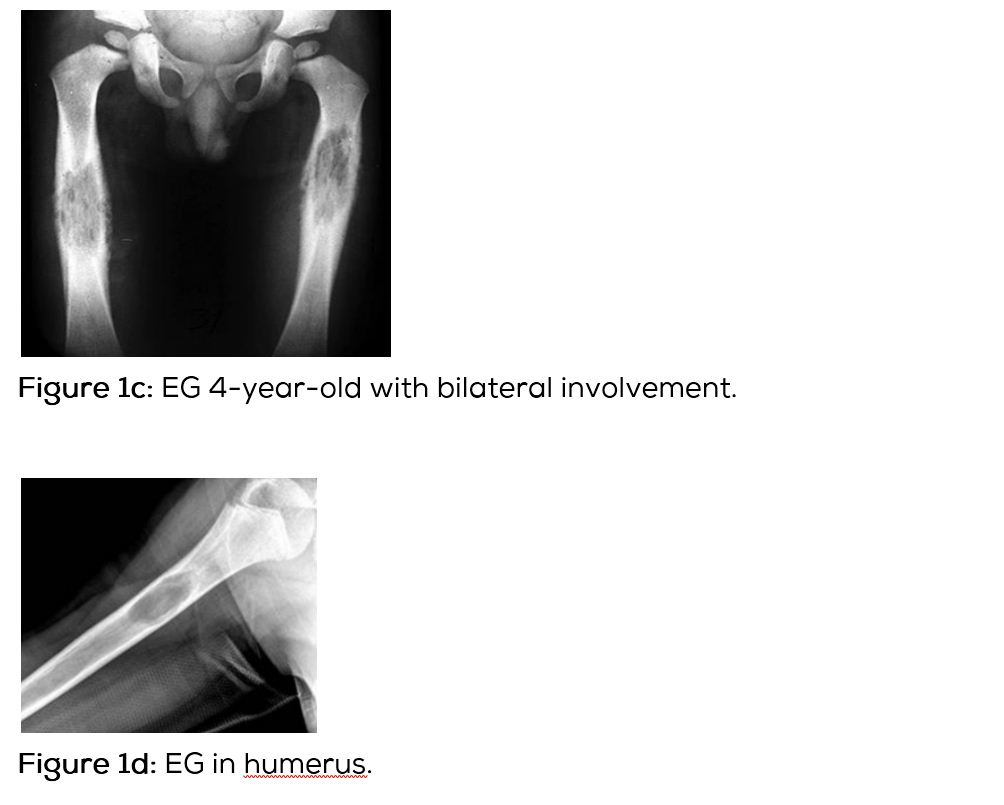

Conventional films show a lytic lesion of varying sizes between 1-3cms. However, multiple lytic lesions in the same bone or in multiple bones may be seen. In the long bones, lytic lesion is round or oval in shape with surrounding sclerosis and thick linear periosteal reaction (Figure 1a,b,c,d,e). In the flat bones such as skull, single or multiple large areas of lysis are seen. The bevelled edges in the skull are due to greater involvement of the inner than the outer table (Figure 1f,g). A button sequestrum is often noted in the lytic lesion (Figure 1h). The size of the lesion may be larger and multiple lesions may be seen. This appearance has been described as “geographical” areas of lysis. The differential diagnosis of multiple lytic lesions of bones of calvaria is listed in Table 1. In the mandible, areas of lysis are seen along the alveolar margin with “floating teeth” (Figure 1i,j). Histopathology shows clusters of eosinophilic cells with admixture of neutrophils and occasional histiocytes (Figure 1k). MRI is not specific but confirms the plain film findings (Figure 1l,m,n).